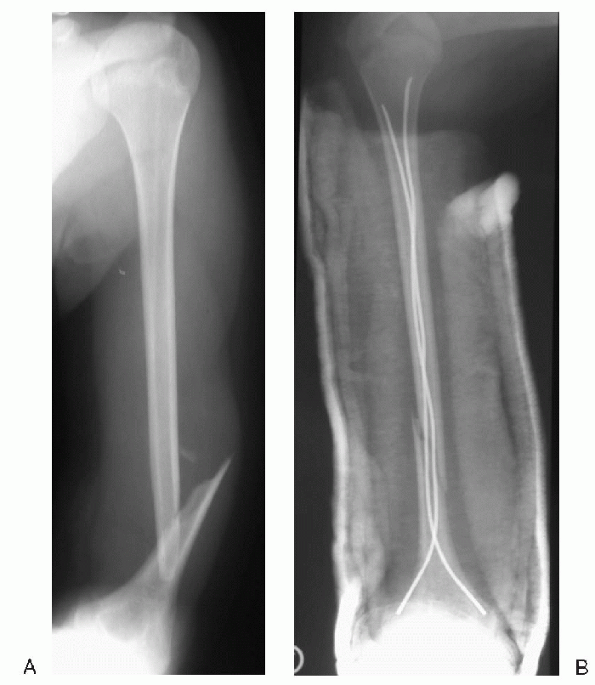

![]() |

Figure 12.2-1 (A) Anteroposterior radiograph of a humerus fracture sustained at delivery in a 4-week-old girl. (B) Complete remodeling seen at 10 months of age.

Figure 12.2-2 (A) Anteroposterior radiograph of a humeral diaphyseal fracture in a 15-year-old girl. (B) Postoperative radiograph after retrograde flexible intramedullary nailing.

The method of choice for fixation of humeral shaft fractures in children is retrograde flexible intramedullary nailing (Fig. 12.2-2).